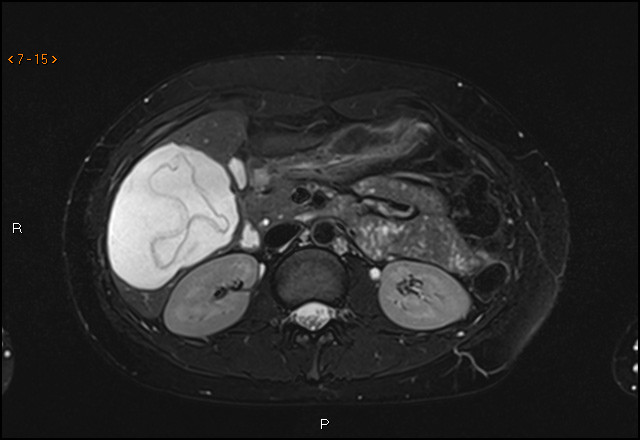

Diagnosen stilles på bakgrunn av typiske bildefunn og antistoffundersøkelse. For å avdekke om det foreligger kompliserende forhold (som rumpert cyste eller fisteldanning til galleveiene) bør cysten også utredes med MR- eller CT-undersøkelse (2). Verdens helseorganisasjon (WHO) har utgitt en ultralydbasert klassifikasjon av ekinokokkcyster, og behandlingen bestemmes ut fra WHO-klassifikasjonen og cystens størrelse (2, 3). Behandlingen består enten av observasjon eller medikamentell behandling med albendazol – alene eller i kombinasjon med aspirasjon og reinstallasjon av parasittdrepende middel (f.eks. hypotont saltvann eller etanol) – eller kirurgisk ekstirpasjon av hele cysten.